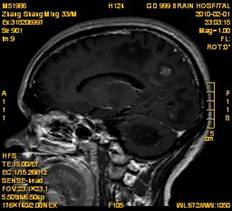

案例2 患者,女,30岁,二氯乙烷中毒性脑病的头颅MR。表现为双侧大脑半球皮层下白质、双侧外囊、双侧苍白球及双侧小脑齿状核内广泛片状、斑片状长T1长T2异常信号影,FLAIR序列呈高信号,增强后病变未见明显强化。

给予抗炎、脱水、疏通血管及营养神经等药物治疗。经过40天的对症治疗,痊愈出院。